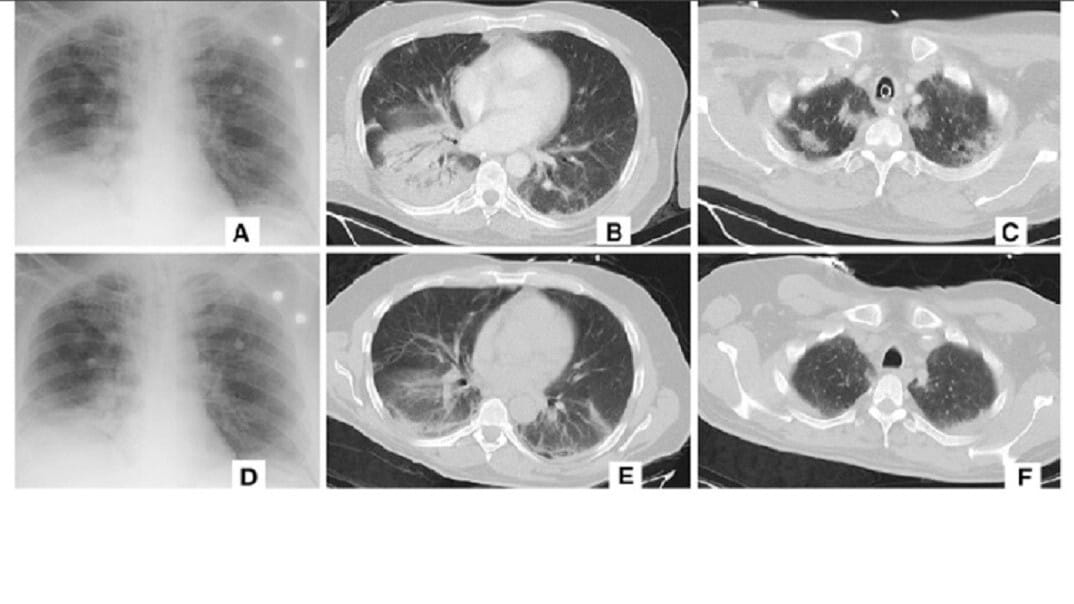

Menurut laporan The Next Web, seperti dikutip Telset.id, Selasa (17/03/2020), sistem baru tersebut bergantung kepada CT scan. Dipadukan dengan AI, maka deteksi virus Corona atau Covid-19 bisa dilakukan dalam waktu yang cepat.

Kecepatan itu jauh lebih efektif dibanding 15 menit atau lebih bagi manusia untuk mendiagnosis penyakit. Alibaba melaporkan bahwa sistem tersebut memiliki akurasi 96 persen untuk deteksi Covid-19.

Untuk melatihnya, sistem dimasukkan gambar dan data berdasarkan 5.000 kasus virus Corona dikonfirmasi di China. Setidaknya 100 fasilitas kesehatan di China sudah menggunakan sistem AI Alibaba.